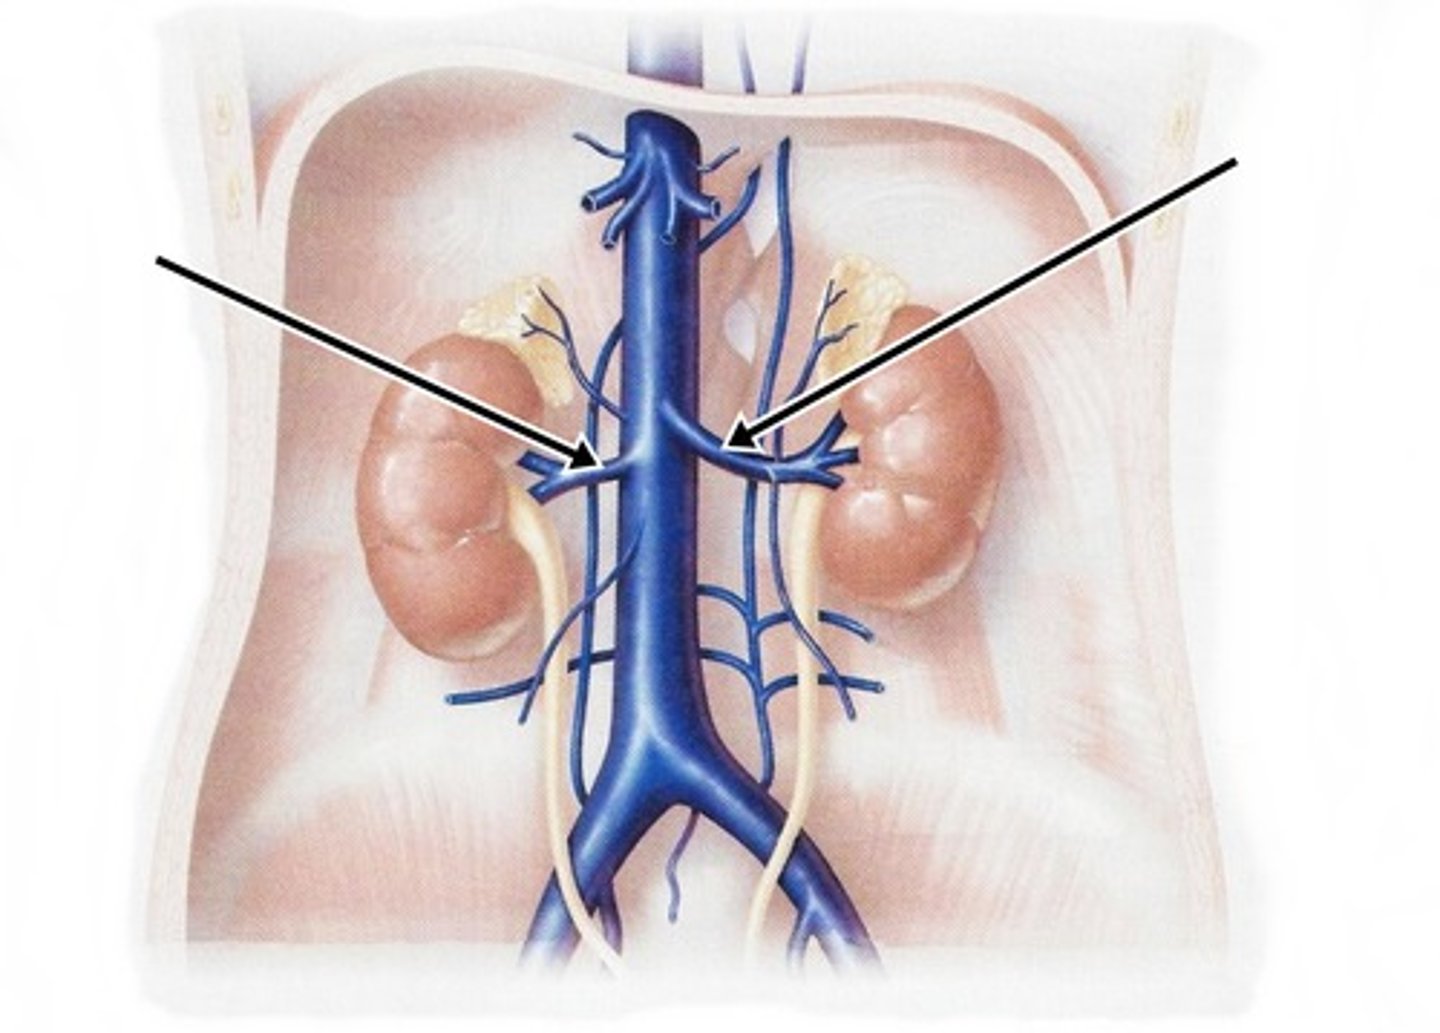

inferior vena cava

renal veins

renal artery

serves the kidneys

common iliac vein